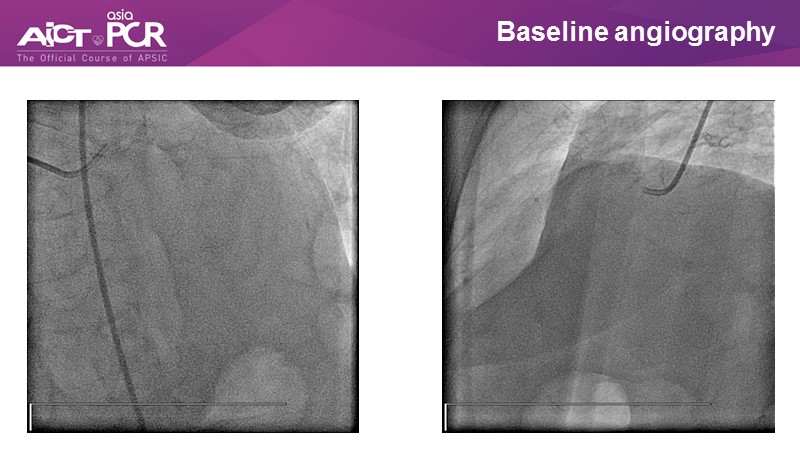

Opening - LIVE demonstration from National University Heart Centre Singapore

Chairpersons: C.K. Naber, M. A. Rosli

Panellists: K. Al Faraidy, K. T. Chan, M. C. Morice, M. Nguyen, T. Santoso, W. A. Wan Ahmad

Operators: A. Low, K. C. Y. So

Control Desk: J. Chen